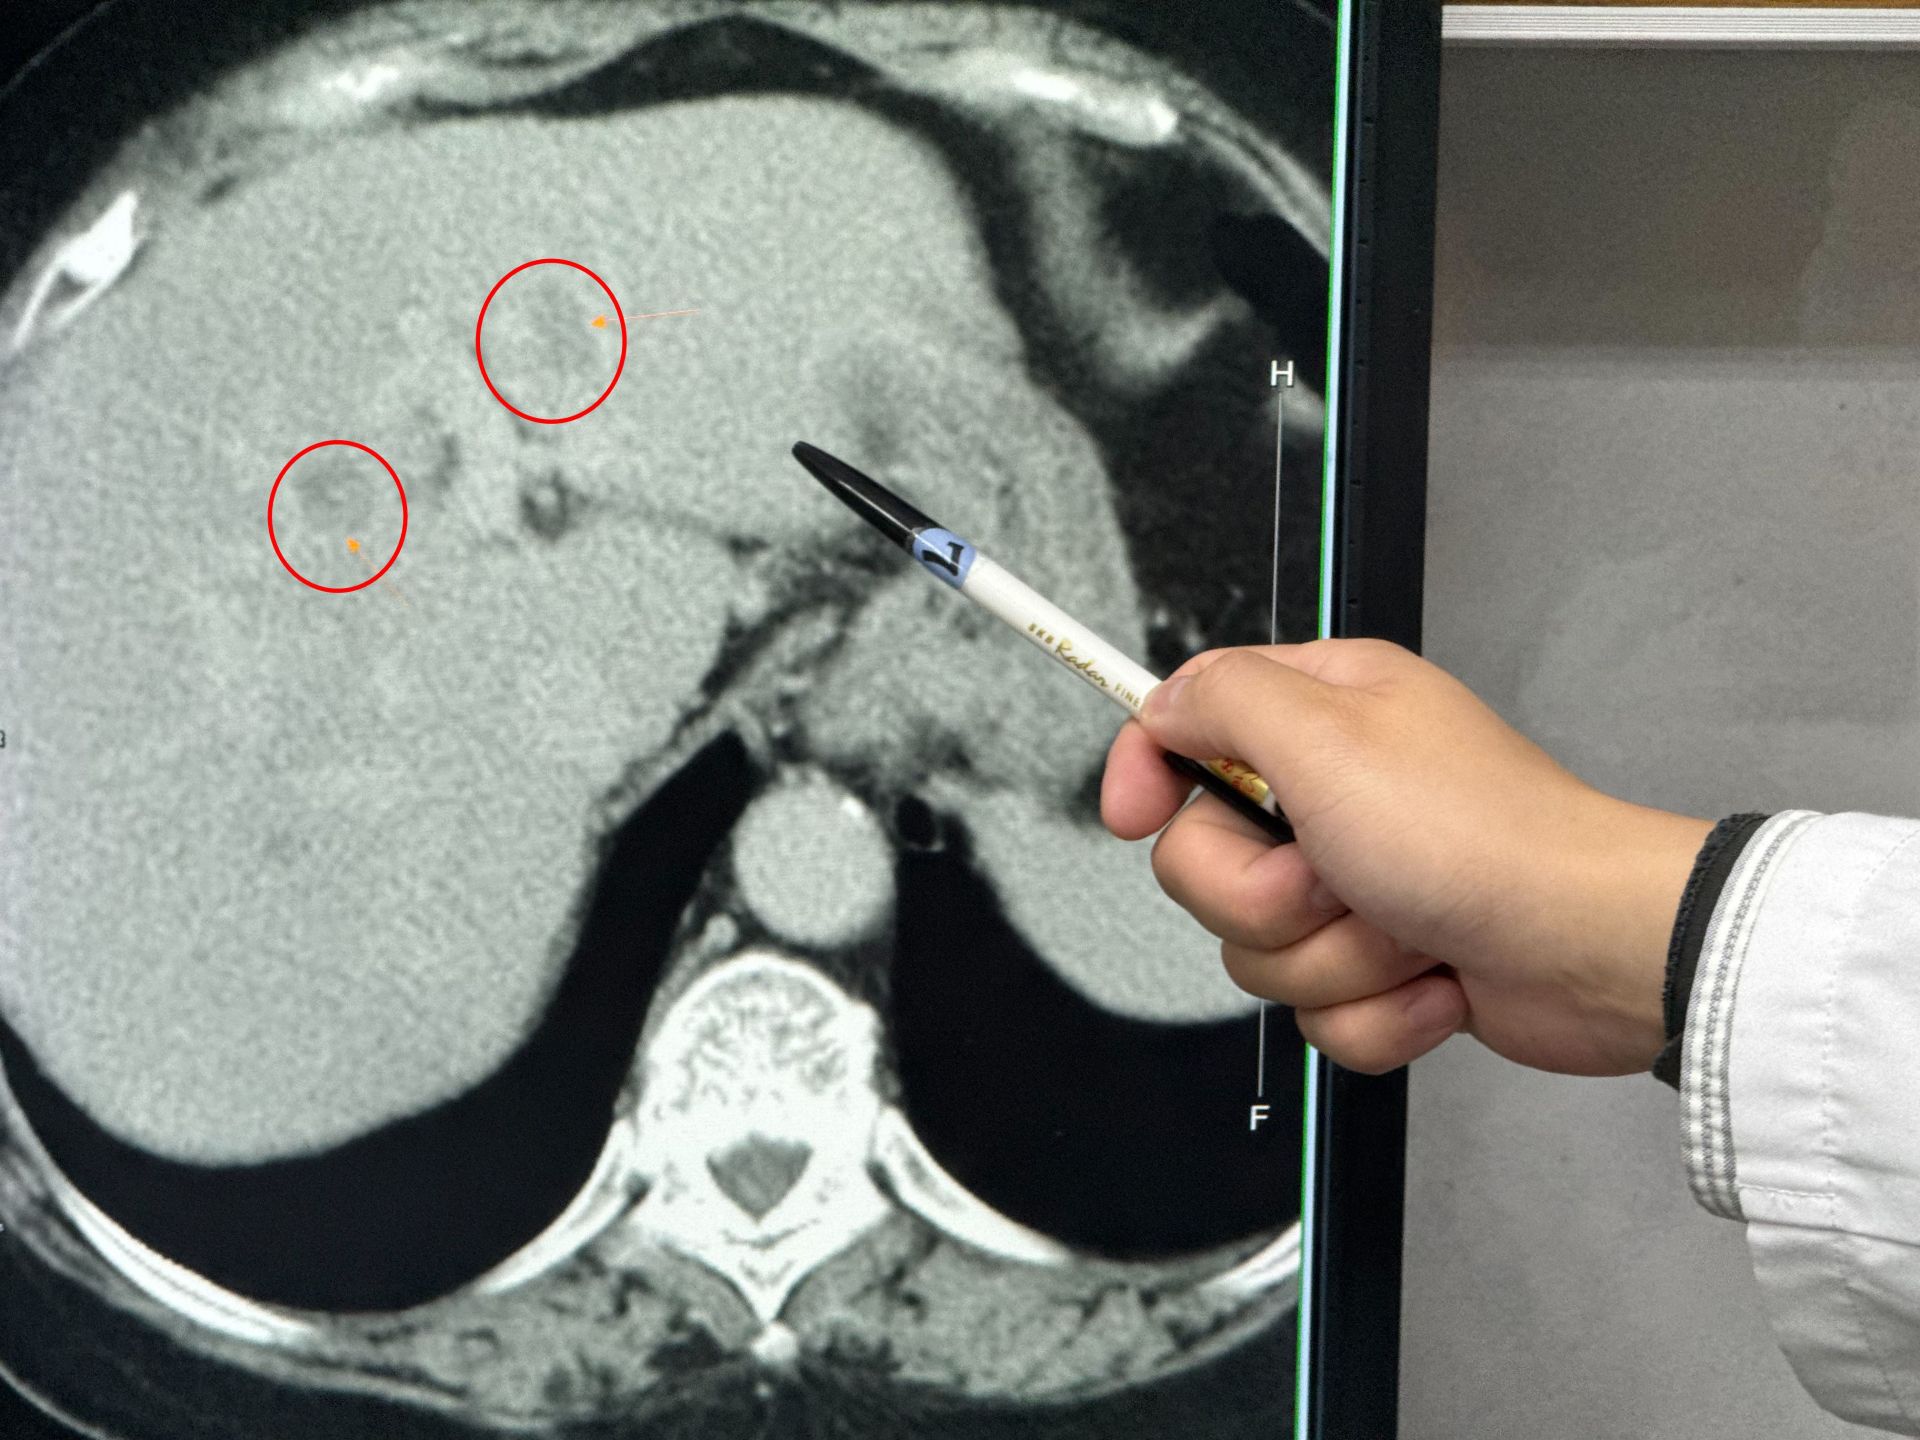

【Lai傳媒 記者爆料網 蔡智銘/台中報導】一名60多歲的婦人,日前到醫院就診意外發現有嚴重的脂肪肝及疑似腫瘤,進一步詳細檢查,在左邊肝臟看到兩顆腫瘤,安排手術治療,醫師手術時驚覺,婦人脂肪肝居然佔肝臟的四到六成以上,術後追問,患者本身沒有喝酒習慣,也沒有B、C肝炎,但是平時很喜歡吃甜食、水果,導致產生重度的代謝異常脂肪肝,甚至病變成肝癌。

患者嗜甜食肝臟檢查出有腫瘤。

駐診在李綜合醫院的臺中榮總一般外科醫師吳坤達表示,婦人在門診腸胃科做超音波時發現有重度脂肪肝及疑似腫瘤,進一步檢查確認在肝臟的左外側葉及左葉中部各有一顆腫瘤,擔心把患者左邊肝臟全切除後,患者肝臟功能恐無法運作,因此,使用「類機械手臂」多關節器械系統切除左外側肝葉,及術中射頻消融治療術消除腫瘤。

吳坤達說明,即使是肝完全健康的年輕患者,肝臟切除手術至少要保留三分之一才能維持基本生理功能,該患者四到六成脂肪肝又有多顆腫瘤,為了讓她的肝臟能正常運作,脂肪肝切下了223克,大約一顆小蘋果的重量,沒有切除的腫瘤則採用射頻消融治療術讓組織壞死,手術進行大約3個多小時,失血量僅有約400CC,患者術後恢復良好。